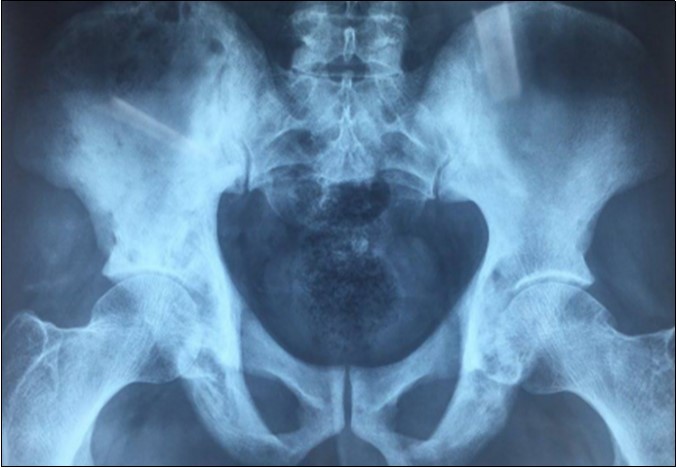

We report the case of an asymptomatic 49 years old male patient, in which a routine check objectified a biological cholestasis (gammagmutamytransferase = 2-3N and ALP = 5-6 N without hyperbilirubinemia or cytolysis). Nos past medical facts were noted. Abdominal ultrasound, viral markers and antibodies measurement (Ac Anti-nuclear, anti-Mitochondrial, anti-LKM1, Anti-cytoplasmic) were normal. Magnetic resonance choalngiopancreatography objectified multiple biliary strictures and parietal irregularities evocative of SC (Figure 1). Colonoscopy showed no associated inflammatory bowel disease. Patient received high doses of ursodeoxycholic acid (20mg/kg) for the SC with partial improvement of liver function but persistence of a marked rise in ALP level. In order to better characterize the nature of ALP, a dosage of ALP isoenzymes was performed and objectified a predominant bone fraction (83%), while liver fractions H1 and H2 were respectively of 12% and 4%. X rays objectified bone condensations with a fibrillar appearance and bone hypertrophy suggestive of PD (Figure 2). A bone scan made for lesions mapping showed a multifocal PD (Figure 3). The patient was treated by bisphosphonates (injections of zoledronic acid), which was associated with a decreasing in ALP level after 6 months.

Figure 2.X ray of the pelvis showing condensations with a fibrillar appearance and hypertrophy of the bone

X ray of the pelvis showing condensations with a fibrillar appearance and hypertrophy of the bone